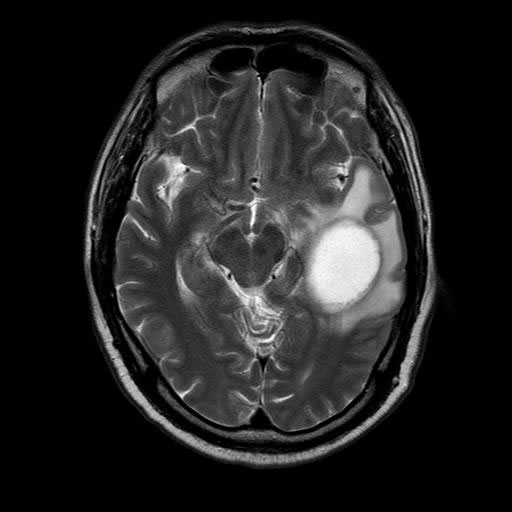

Figure 1: In September 2016, MR scan showed brain occupancy.